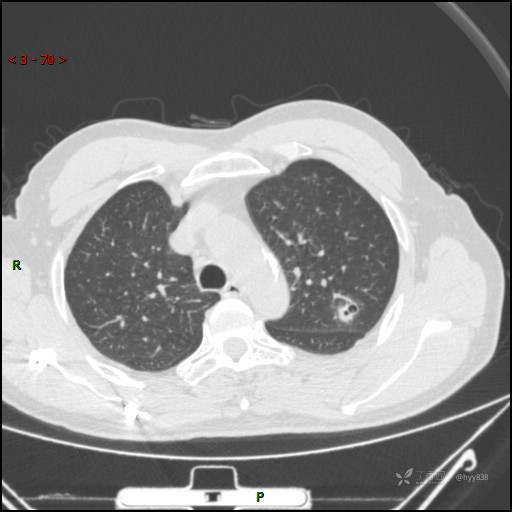

又遇恼人的肺结节,囊腔 VS 空洞 VS 空泡,欢迎讨论---结果公布~

患者年龄:61岁

主诉:发现左肺结节半月

简要病史:患者半月前因双眼翼状胬肉于我院眼科就诊行手术治疗,完善胸部CT发现左肺结节,未行特殊处理,偶有刺激性干咳,每于受凉后及饮冷水后发作,休息后可自行缓解,无发热、恶心呕吐、胸痛咯血,现为求进一步诊治,于我院就诊,门诊以“左肺结节”收入我科。 起病以来,患者食欲尚可,大小便正常,睡眠、精神可,体力、体重无明显变化。

临床诊断:肺结节

胸部CT平扫